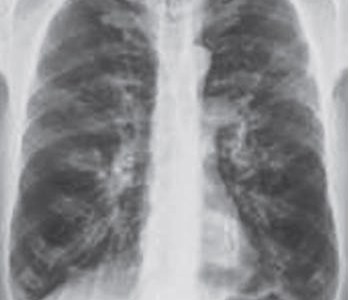

Image challenge-1- Answer

Image Challenge ,